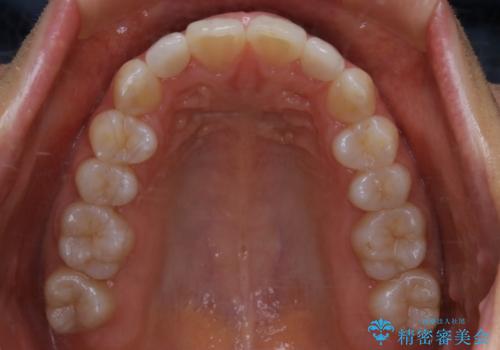

- 上の前歯が大きい事と下の前歯のがたつきを気にされてご相談にいらした方です。上の2番目の歯が矮小歯であったため、矯正治療にて歯のスペースを作った後、矮小歯には被せ物をして前歯のバランスを整えました。

歯科技工士さんとの打ち合わせを重ね、周囲の歯としっかりなじむ天然歯のような被せ物をお作りすることが出来ました。

矯正治療と補綴治療をうまく組み合わせることで、美しい口元に仕上げることが出来ました。矯正治療、補綴治療をまとめて行える総合歯科治療を体現した治療といえます。